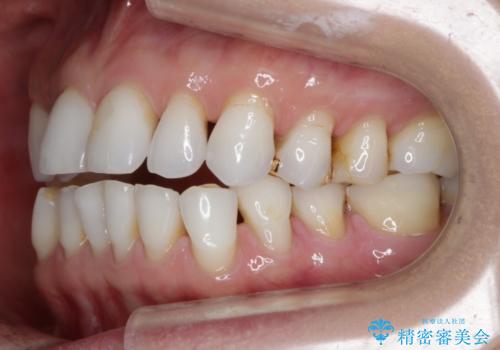

【非抜歯】マウスピースでオープンバイトを治す

- 歯ぎしりや食いしばり、噛み合わせの治療とガタつきを治したいとのことでご来院されました。

検査の結果、前歯と臼歯の高さに差があり、前歯が全く当たらない状態になっているため歯ぎしりによって奥歯が削れてしまっているという状態でした。

マウスピースの矯正装置を用い、ガタつきを治しつつ奥歯を沈めていくことで噛み合わせ全体の改善を図りました。